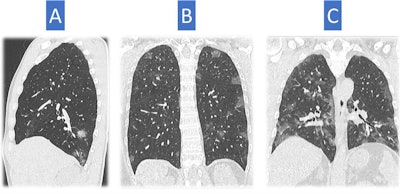

CT scans of three different patients depict typical findings for COVID-19 pneumonia. These look different in severity. Image A shows patchy rounded ground-glass opacities, essentially distributed in the right lower lobe. This is not an unusual feature of infection; therefore, it is difficult to make a differential diagnosis with x-ray. Image B shows several ground-glass opacities, rounded in shape and distributed mainly in the superior regions of the lung, a classic distribution of COVID-19 pneumonia-related abnormalities. Image C depicts ground-glass opacities that are more severe in extent with patchy distribution, occupying a greater volume of the lung. All findings are typical of COVID-19 pneumonia but are not very specific. All images courtesy of Dr. Nicola Sverzellati.Moderator Dr. Adrian Brady from Mercy University Hospital in Cork, Ireland, posed further questions from European Society of Radiology (ESR) members pertaining to the role of plain chest x-ray and other modalities, suggesting it might be reasonable to consider that if CT is available, there may be little or no role for x-ray diagnosis.